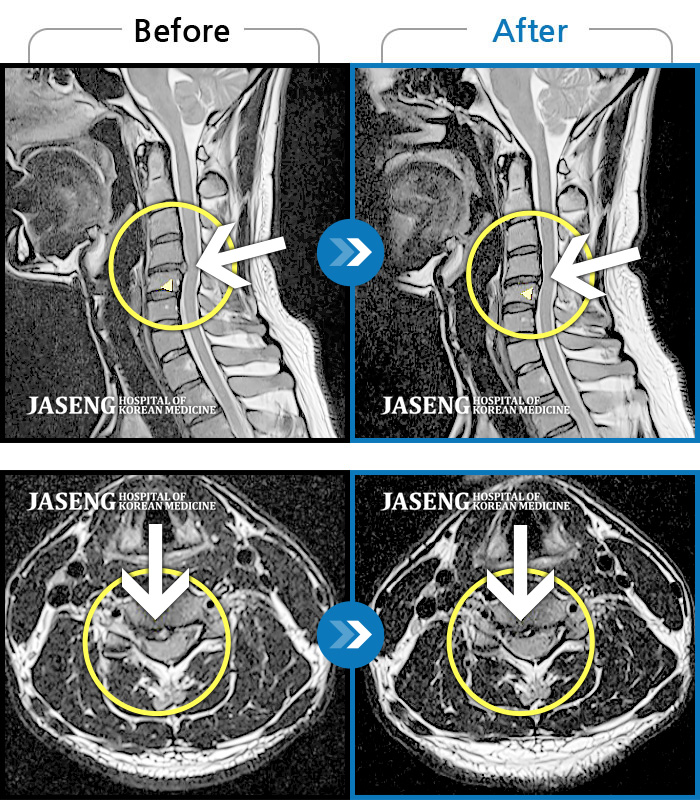

자생 비수술 한방통합치료 후

터진디스크가 흡수된 모습

목 통증과 새끼 손가락 저림 및 안정시에도 우측 어깨 통증 호소하여 내원하셨습니다.

2022.08.10 ~ 2024.11.08